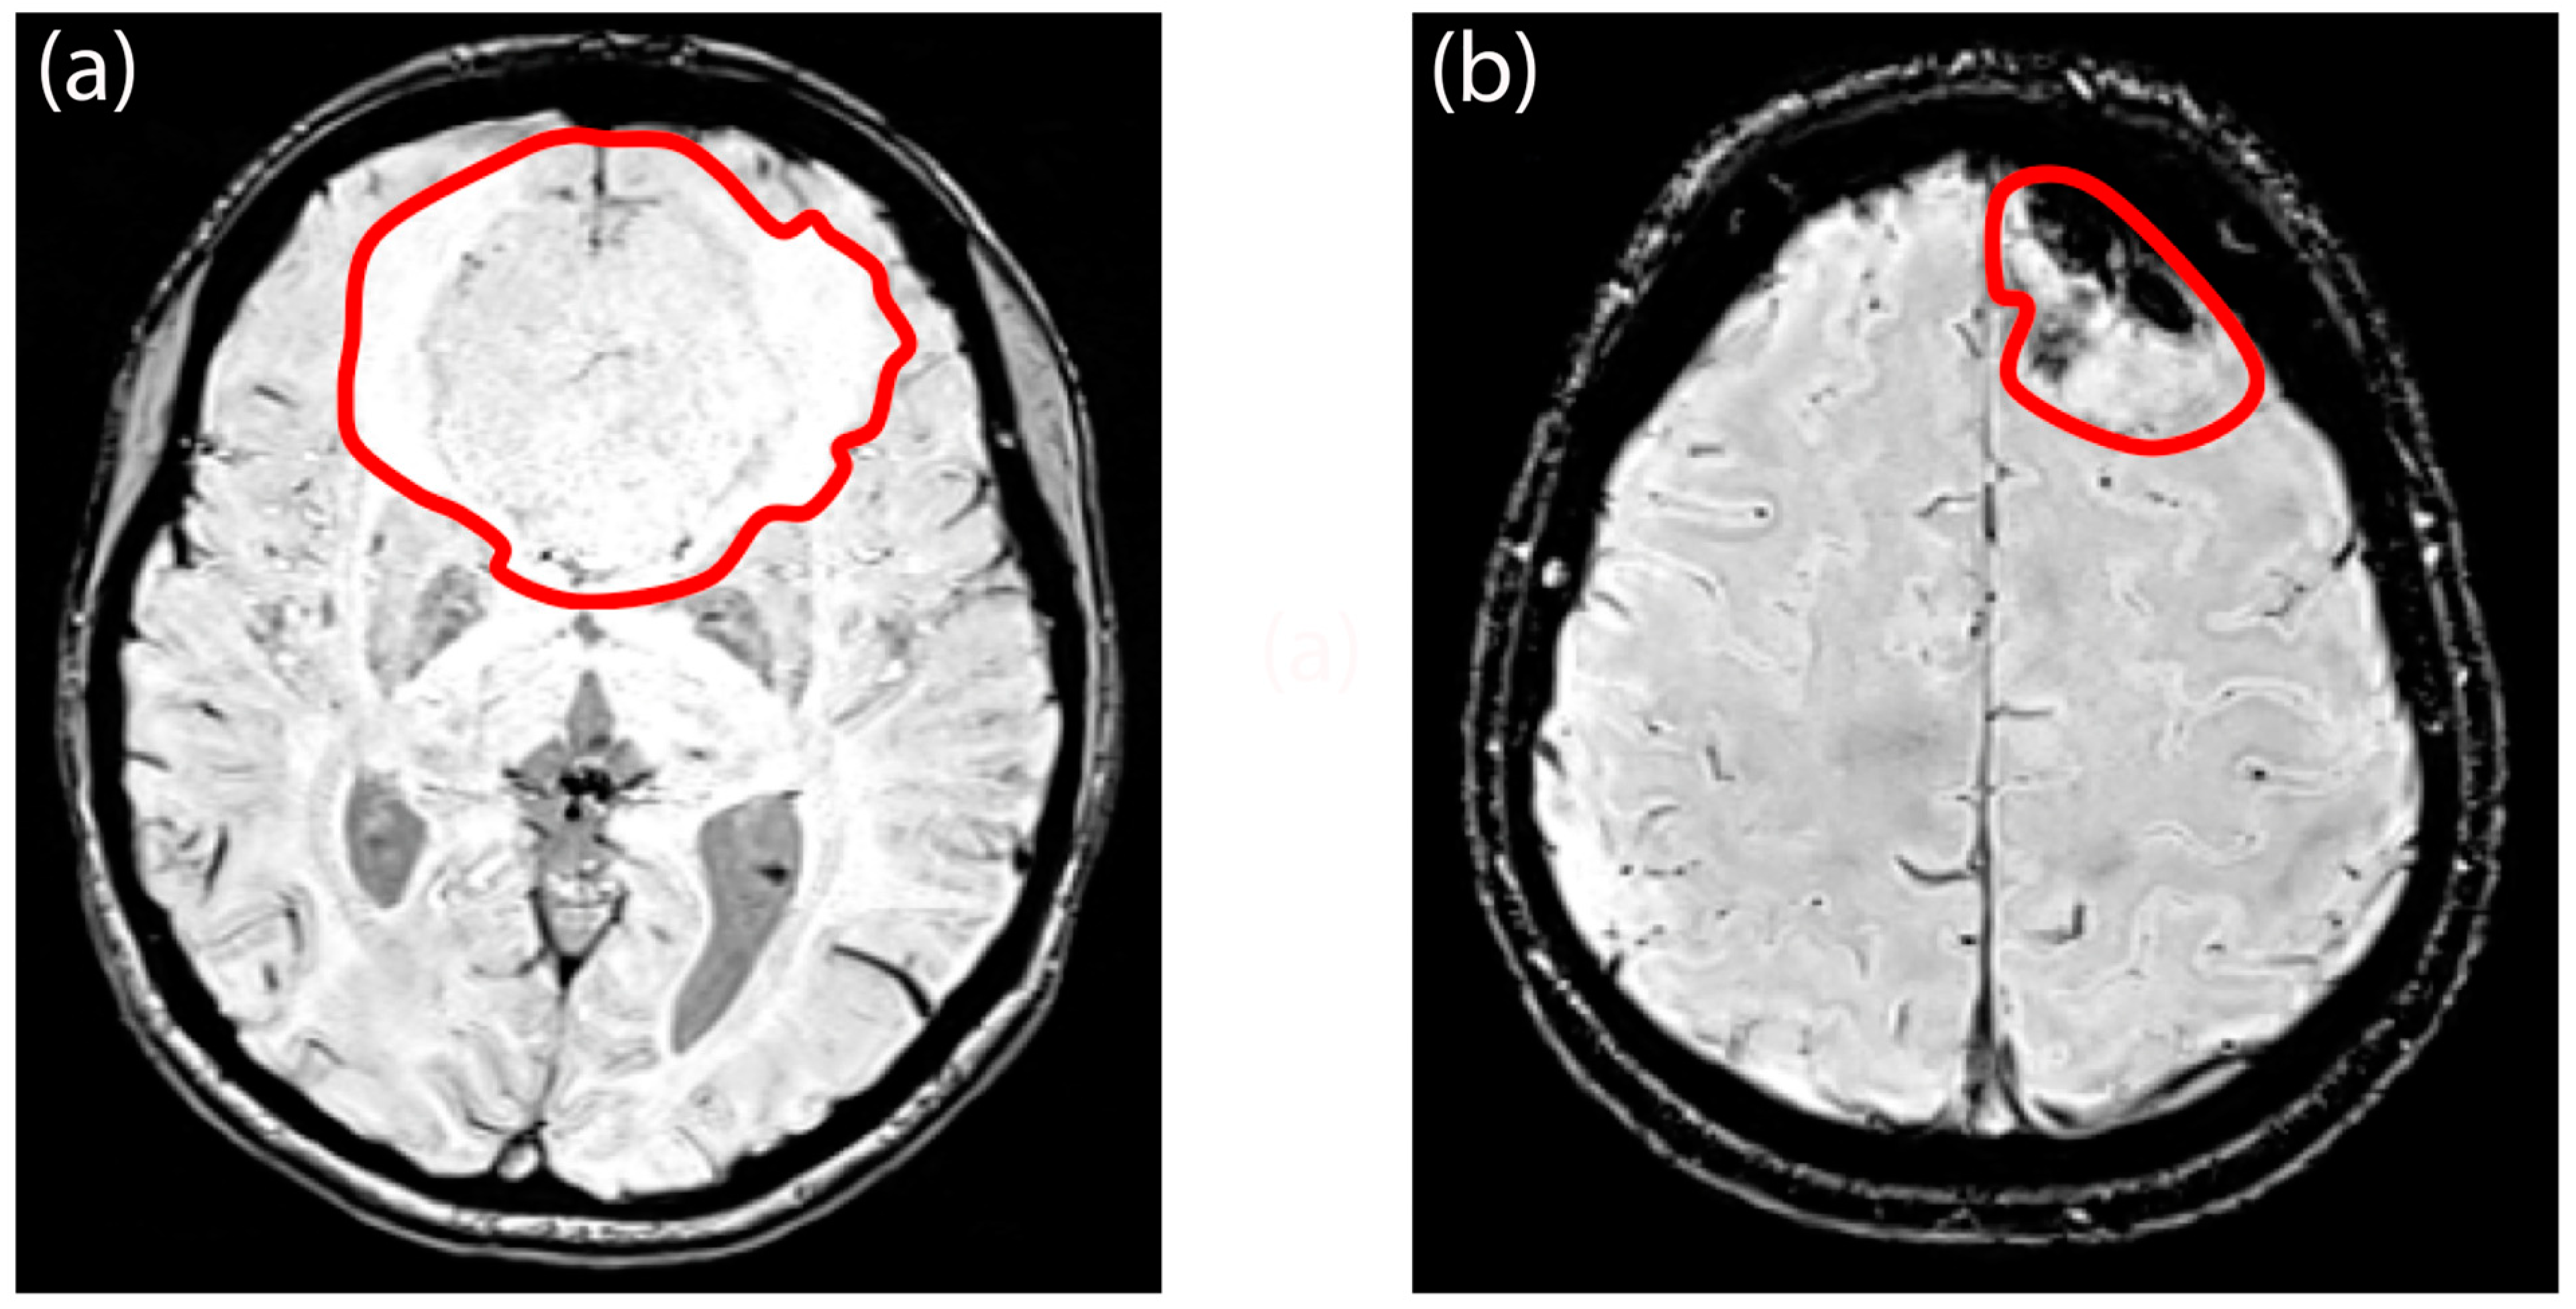

2.5. Image Processing